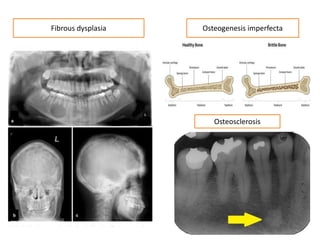

Osteogenesis imperfectaFibrous dysplasia

Osteosclerosis